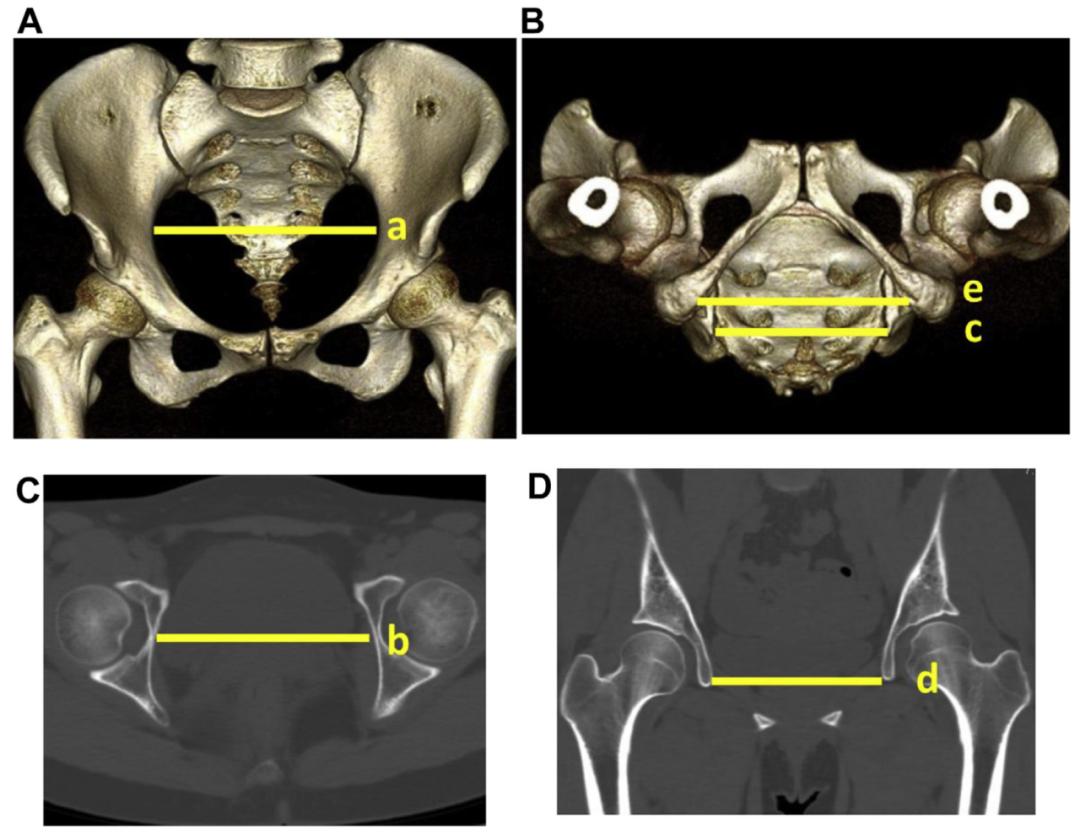

换句话说,大家更关心的是,做过这个手术,还能顺产吗?如图所示,能否经阴道分娩取决于骨盆通道最狭窄的位置。

国外有相关的骨骼测量研究,一些做过该手术且尚未怀孕的女性患者,通过测量她们的骨盆CT或核磁,结果显示产道的前后左右径均变化不大。

这说明髋臼截骨手术没有明显让骨盆变窄。但这可不敢保证孩子就一定能顺产。因为影响孩子分娩方式的因素比较多。